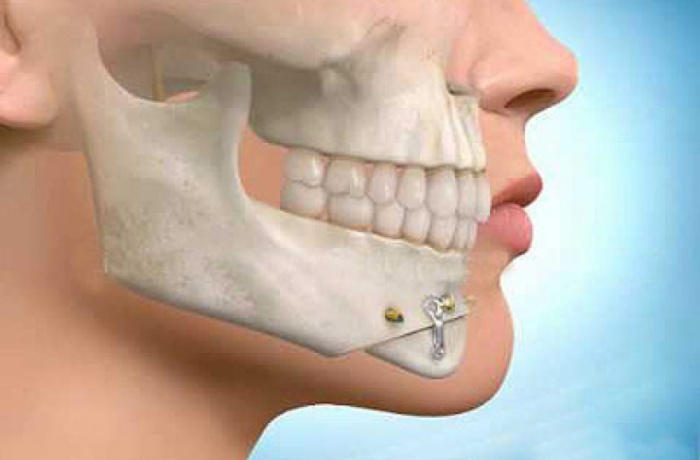

SONNY SERITE Renowned Gaborone medical practitioner Dr. Motsholathebe Phuthego has come out vehemently to quash suggestions he could be practicing as Specialist Oral and Maxillofacial Surgeon without appropriate academic qualifications in that…

SONNY SERITE The Botswana Health Professions Council (BHPC) was established in accordance with the Botswana…

SONNY SERITE “Heart patients may be putting their health at risk by taking treatment from…